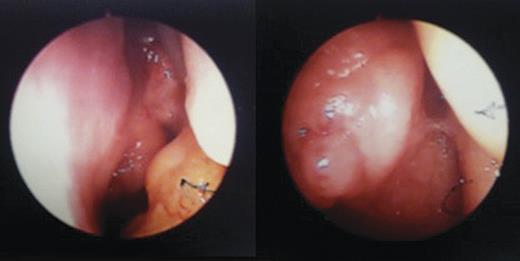

A 31-year-old teacher was referred by her General Practitioner (GP) for investigation of an 18-month history of left-sided fluctuating hearing loss. No other otological symptoms were reported. The patient had a history of focal migraines and polycystic ovary disease and took no regular medication. Initial physical examination revealed rhinitic-like mucosa bilaterally. Otoscopy and audiometry suggested a unilateral otitis media with effusion and unilateral conductive deafness, respectively, with subsequent flexible endoscopy revealing a cystic lesion (Fig. 1) obstructing the Eustachian tube opening.

Images from left-sided rigid endoscopy demonstrating an abnormal cystic mass.